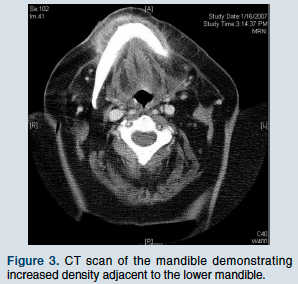

The complete blood count demonstrated a hemoglobin of 9.4 g/dL and a hematocrit of 30.1%. The corpuscular indices were within normal limits; the white blood cell count was within normal limits at 10,000 with 81% neutrophils, 10% monocytes, 0% basophils, and 7% lymphocytes. The platelet count was 232 x 103/µL. Glucose was 103 mg/dL, BUN 18 mg/dL, creatinine 1.0 mg/dL, sodium 138 mEq/L, potassium 4.7 mEq/L, chloride 106 mEq/L, bicarbonate 23 mEq/L, AST and ALT 16 U/L, alkaline phosphatase 50 U/L, calcium 8.8 mg/dL, albumin 3.4 g/dL, and total protein 5.7 g/dL. The computed tomography (CT) scan of her mandible (Figure 3) was read as: “Submandibular soft tissue swelling at the level of the mandibular symphysis, more on the right than the left. The possibility of small submandibular abscesses cannot be excluded. No etiology is identified.”